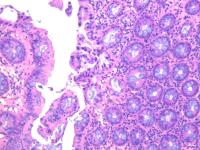

横结肠息肉

性别年龄56临床诊断

一般病史体检

标本名称横结肠息肉

大体所见灰白2粒

肠粘膜息肉。

小灶区域腺上皮有异型,重切一张再看看。

表面黏膜上皮有很少异型细胞。间质中一团上皮样细胞性质不明,没有明显异型性。可描述发报告。